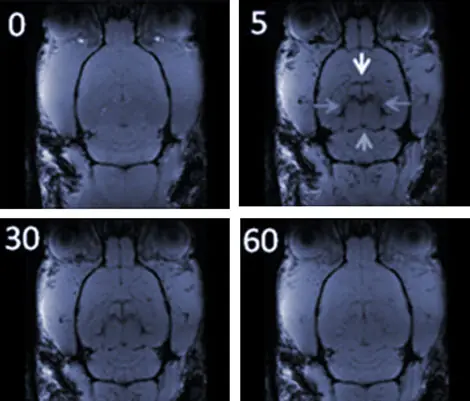

P. M. También estamos estudiando la capacidad de las nanopartículas de óxido de hierro para mejorar el contraste en las imágenes de tejido interno. Por ejemplo, las imágenes inferiores muestran el cerebro de una rata por Resonancia Magnética de Imagen. A tiempo 0 (imagen superior izquierda), en ausencia de nanopartículas, no se diferencian las distintas partes del cerebro. A los 5 minutos de la inyección, tal y como se muestra en la segunda imagen comienzan a distinguirse (flechas) y al cabo de 60 minutos las nanopartículas ya han desaparecido del cerebro.